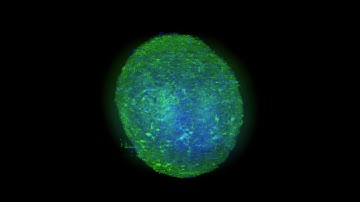

OpenLiver HepaRG NP 3D: MDR1 Labeling and Tissue Clearing